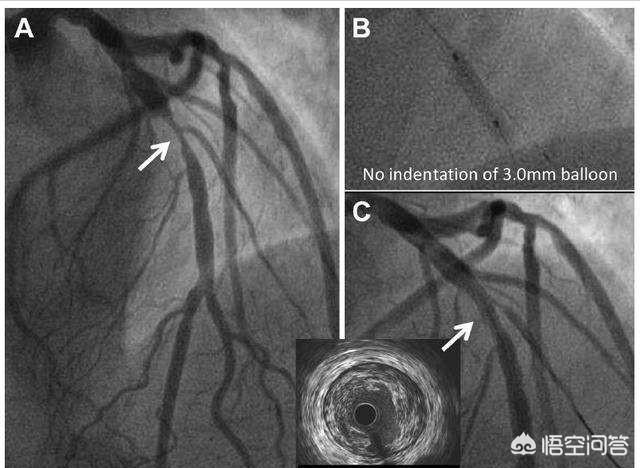

5.超音波検査と血管内超音波検査:心臓超音波検査は、心臓の心室壁の動き、左心室の機能と形態を調べることができ、この方法は現在最も一般的に使用されている検査手段の一つである。乳頭筋機能、心破裂、腔内血栓、心室壁腫瘍などの診断に重要な価値を持つ。血管内超音波検査は、冠動脈内の狭窄の程度や壁の形態を明らかにすることができ、これは有望な新技術である。

6.核種心筋イメージング:この検査は、病歴から心電図検査で狭心症が否定できない場合に行われる。核種心筋イメージングは虚血領域を示し、虚血の位置と範囲を明確にすることができる。運動負荷試験と画像診断を併用することで、発見率を向上させることができる。

冠動脈造影を行う場合は、次のような方法もある。血管内超音波動脈硬化プラークを判定する検査